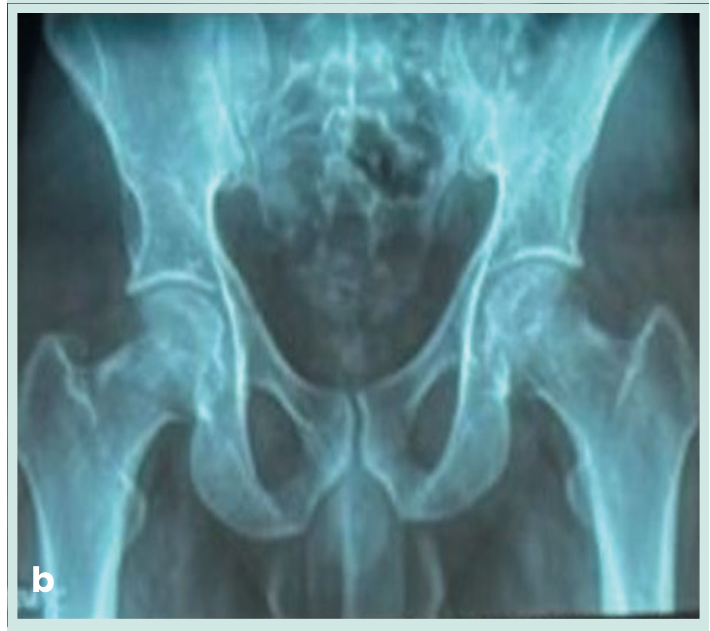

• Estudios complementarios: uretrocistografía retrógrada: contorno regular de la uretra, sin defectos de llenado ni reflujo vesicoureteral (Figura 2a, 2b y 2c). Panel de infecciones de transmisión sexual por PCR: negativo. Procedimiento: se realizó exéresis quirúrgica completa de la lesión bajo anestesia local.